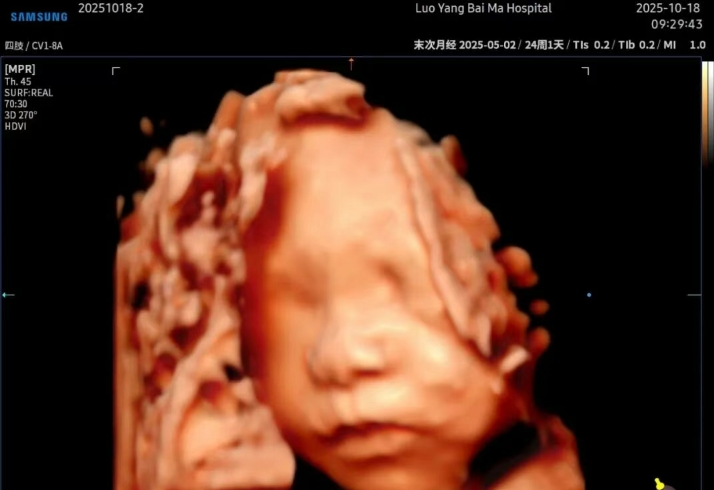

洛阳白马医院5D智能彩超,是目前先进的超声诊断技术,

广泛运用于对胎儿进行超声检查,具有智能化大数据分析诊断和人性化智能交互应用功能,

相比四维彩超,在排畸功能上更完善、观察范围更广、画面更清晰,能够多方位、

多角度观察宫内胎儿生长发育情况。

能栩栩如生的显示您未出生的宝宝在妈妈肚子里的实时动态。

洛阳白马医院5D智能彩超+AI成像增值服务套餐,

通过四维彩超中宝宝的脸型,头型,五官位置等信息,利用人工智能算法,

大致测算并画出宝宝的样子,预测宝宝出生后的长相,并且将宝宝的图片处理得更清晰、

皮肤质感更逼真,满足父母对宝宝第一张“写真”的美好期待。